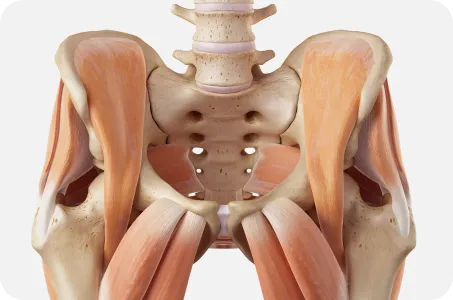

골반이 틀어지면

온몸이 무너진다.

골반은 보행시 지면에서 올라온 충격을 척추로 전달하고

상체의 무게를 고관절과 하지로 전달하는 역할을 하기 때문에

힘전달의 중심축의 역할을 합니다.

골반이 틀어지면 척추와 어깨, 고관절, 무릎이 같이 틀어집니다.

골반은 허리와 다리를 연결하는 상하체 균형의 핵심 역할을 합니다.

우리의 몸은 한 곳이 틀어지면 연결되어있는 다른 곳도 틀어질 수 있습니다.

따라서 거북목, 일자목, 굽은등, 허리뼈의 틀어짐은 골반부터 교정해야 진도가 나갈 수 있습니다.

요추 –골반- 고관절 복합체인 3개의 축을 동시에 교정하니까

골반은 위로는 척추와 어깨, 아래로는 고관절 및 발, 무릎까지 연관이 있습니다. 틀어진 골반만 교정하는 것이 아니라 골반틀어짐으로 인해 생긴 척추와 고관절 무릎까지 넓게 보고 교정하기 때문에 골반교정으로 몸 전체의 척추관절이 교정되는 효과를 볼수 있습니다.